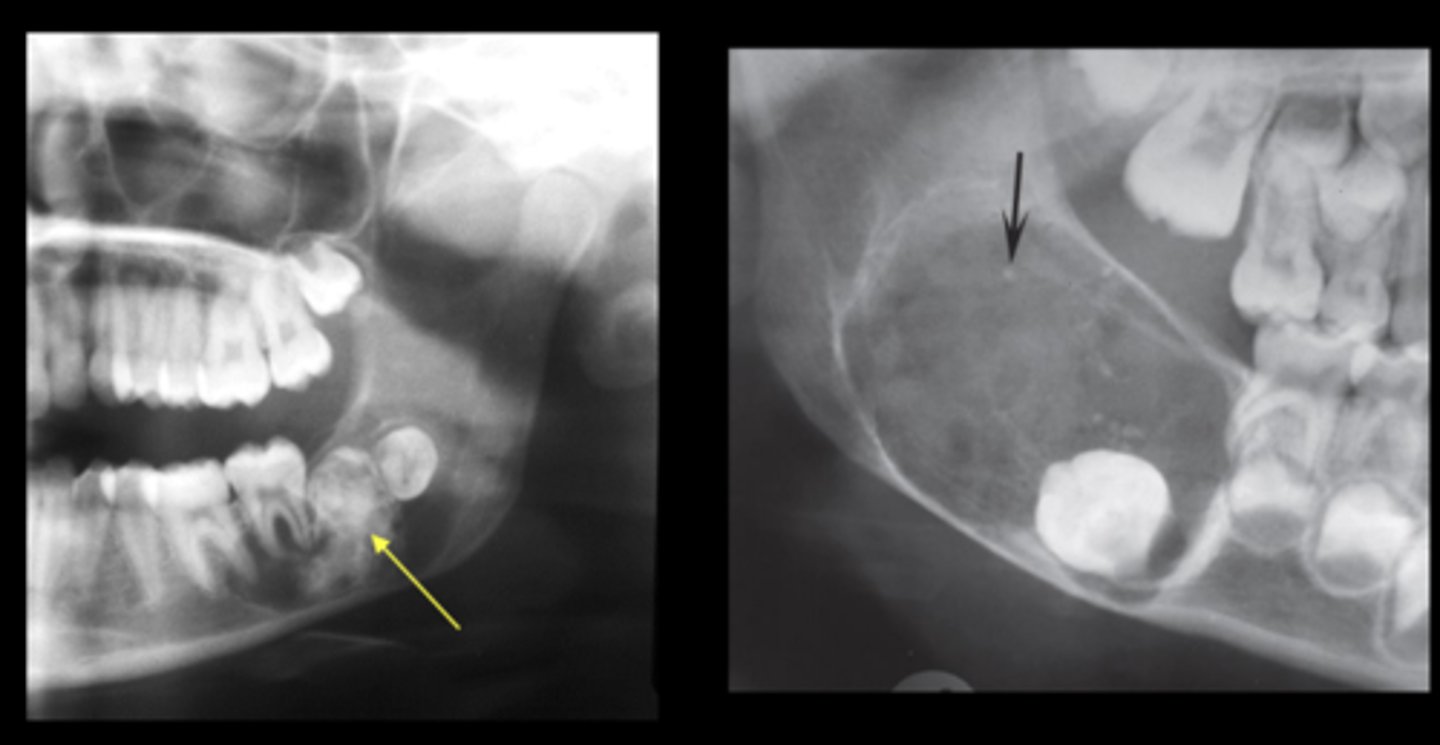

What are the radiographic features of ameloblastomas?

⢠unilocular radiolucency (early lesions)

⢠multilocular radiolucency (honeycomb/soap bubble) (large lesions)

⢠cortical thinning/bone expansion

⢠resorption of adjacent tooth roots + tooth displacement

What is the treatment & prognosis of an ameloblastoma?

⢠treatment: surgical excision - resection for large lesions

⢠prognosis: guarded -- 55-90% recurrence (15% if resection)